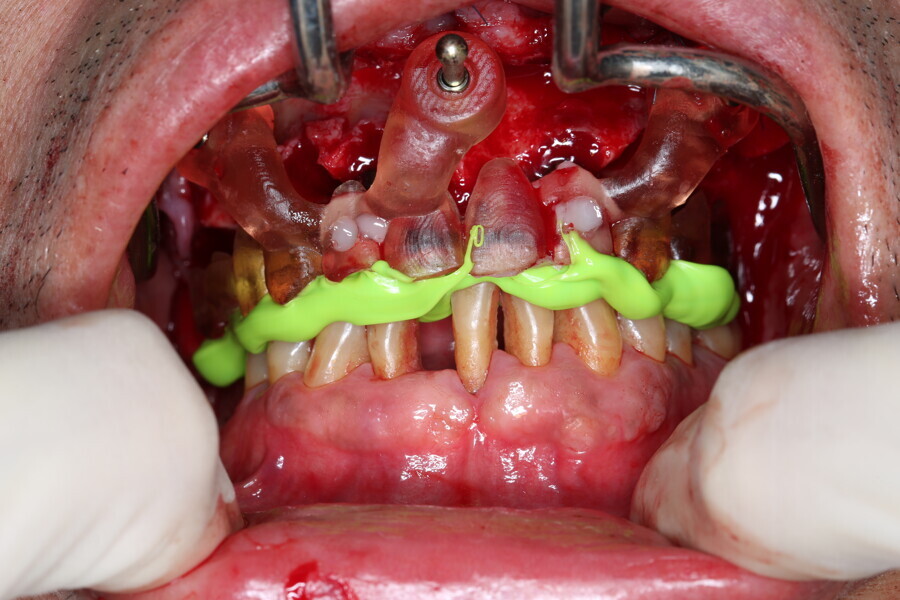

Compromised maxillary dentition treated with Straumann Pro Arch and a digital workflow